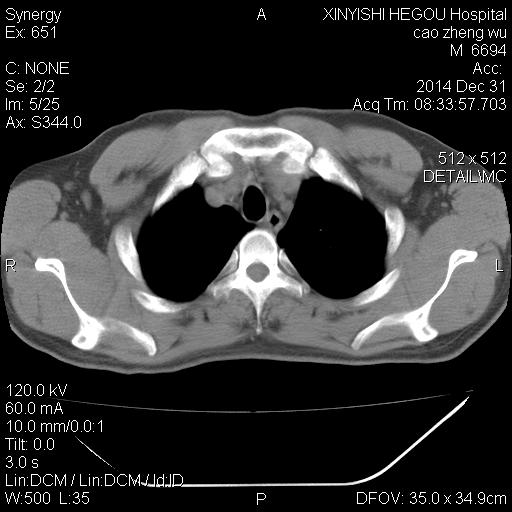

CT49662:男,38岁

右肺下叶结节影

未见异常

没看出问题。